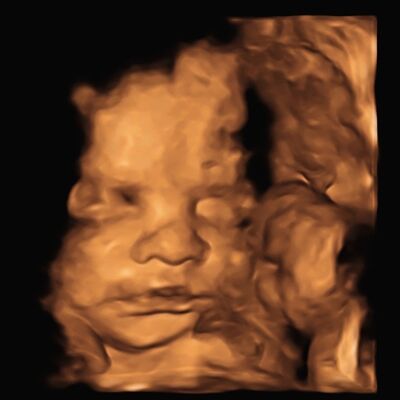

Dilay'ın gebelik günlüğü: 22. hafta

Hamileliğin 22. haftasına dair bir şeyler okumak istiyorsanız Gebeliğin 22. Haftasında Neler Oluyor? içeriğimize davetlisiniz!